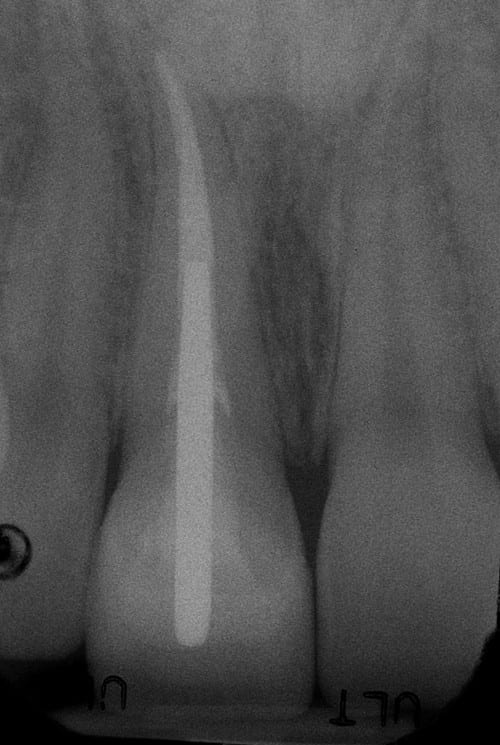

After: Followed by delivery of a custom ceramic post/core foundation, and a bonded all-ceramic full coverage single restoration (crown).